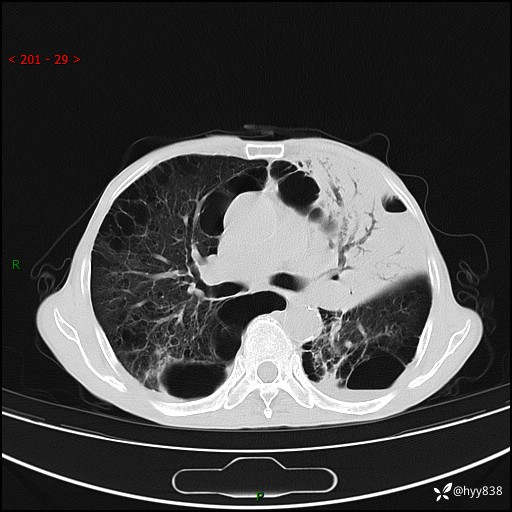

老年男性,反复咳嗽、咳痰、气喘10余年,再发3天。大叶性实变+胸膜病变-结果公布

主诉:反复咳嗽、咳痰、气喘10余年,再发3天

现病史:患者于10余年前开始出现反复咳嗽,咳痰,偶有少许黄色粘痰,伴活动后气喘,多于受凉及天气变化时发作,无胸痛、心悸、咯血等症状,休息后可自行缓解,起初因症状轻微可耐受,未到医院诊治,后症状逐渐加重,频发活动后气喘,活动耐力逐渐下降,未予药物治疗。3天前患者腹泻后出现气喘加重,伴咳嗽,咳黄色粘痰,痰较多,不易咳出,食欲差,无发热,无头昏、乏力、心慌,无头痛、晕厥,无端坐呼吸,无咯血,无胸痛、腹痛,无下肢水肿等,为求进一步诊治,来我院,急诊以“慢性阻塞性肺疾病伴急性下呼吸道感染”收入我科。 本次急性发作以来,患者精神、食欲差,大小便如常,体力下降。体重无明显变化。

胸部CT平扫+增强